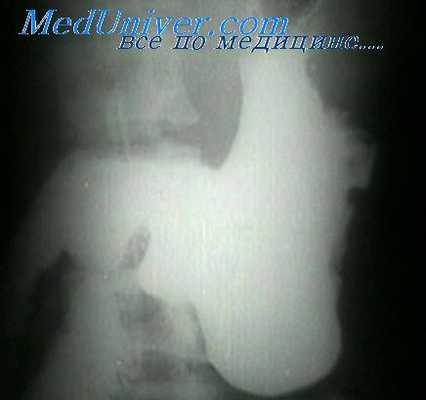

Рентген по Тренделенбургу

Для проведения исследования пациенту следует принять специальную позу – таз должен быть приподнят, находиться под углом 30–35 градусов по отношению к голове.

В таком положении кишечник опускается в грудную полость, барий проникает в кишку, что позволяет чётко увидеть контуры органа. Процедура открывает доступ к малому тазу, с её помощью можно не только выявить грыжу, но и удалить её оперативным путём.